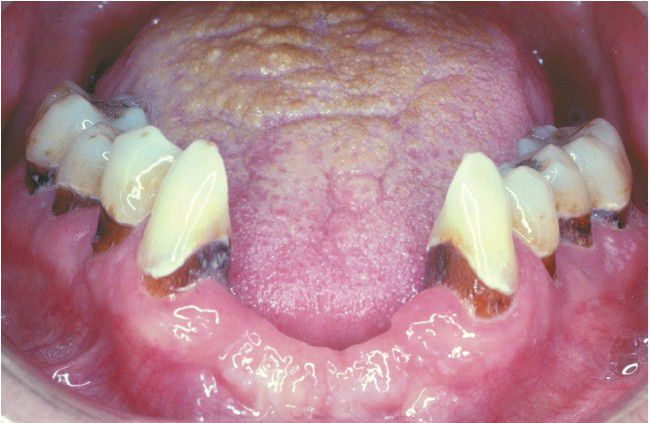

Xerostomia-related Caries.

Extensive cervical caries of mandibular dentition secondary to radiation-related xerostomia.

Caries

Cervical

Xerostomia